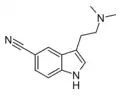

| 5-CN-DMT | artificial | 5-C≡N | CH3 | CH3 | 5-cyano-N,N-dimethyltryptamine | 17380-42-6 |